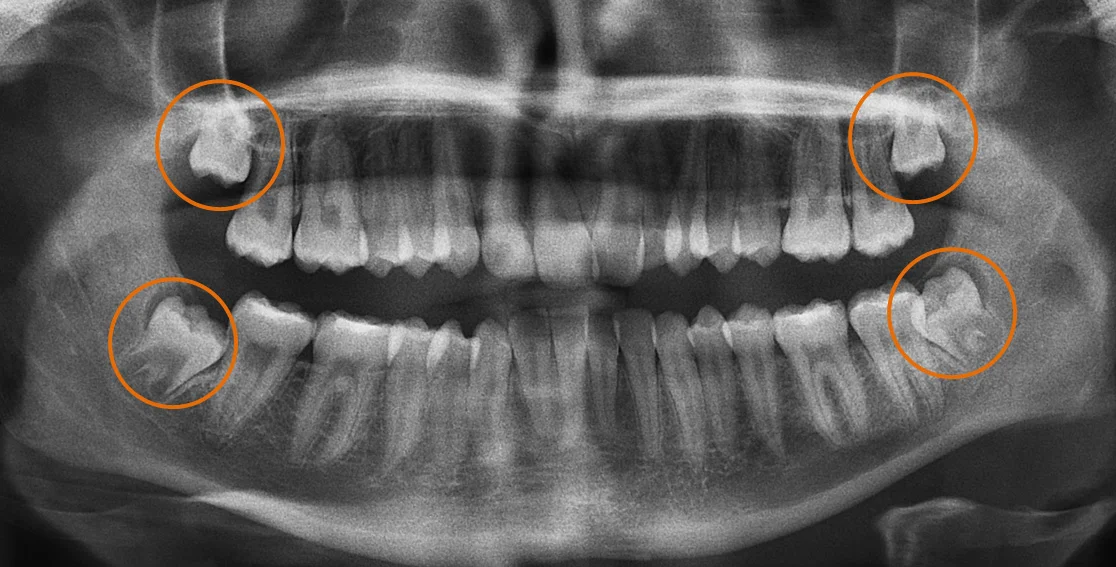

Panoramic X-rays: The Standard Tool

Panoramic x-rays create a single, flat image showing your entire jaw—all teeth, sinuses, and bone structure in one view.

For wisdom teeth, panoramic x-rays show:

- Whether wisdom teeth exist and their general position

- Approximate nerve canal location

- General proximity of roots to nerve

- Whether infection or cysts are present

What Panoramic X-rays Cannot Show

The critical limitation is dimensionality. Panoramic x-rays are two-dimensional projections of three-dimensional anatomy.

You cannot determine:

Whether the nerve runs in front of, behind, or between wisdom tooth roots. The 2D image collapses three-dimensional relationships—you see that nerve and root overlap on the x-ray, but don’t know if they’re touching or separated by millimeters with one in front of the other.

Exact root configuration. Roots might curve toward the nerve, wrap around it, or diverge away—impossible to determine from a single flat view.

Bone thickness between nerve and root. There might be substantial separation, paper-thin bone, or direct contact—indistinguishable on 2D imaging.